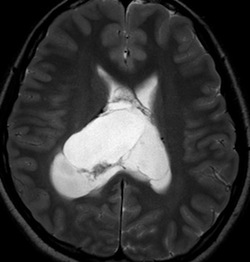

20代の男性の神経細胞腫です。側脳室の中のとても大きな腫瘍です。上段はガドリニウムという造影剤を入れた時のMRIです。下段の中央はCTですが,石灰化が見られます。脳外科の先生には,この脳室内腫瘍は一見transcallosal approach(経脳梁到達法)という手術で取れるように見えるかもしれませんが,そうではなくて,脳室の壁とくに上壁と側壁にくっついているのでなかなか取れません。この患者さんの場合は右の頭頂葉というところからtranscortical approach(経皮質到達法)で全摘出しました。後遺症もなく再発もなく術後10年が過ぎています。全部とれれば治ってしまう腫瘍です。